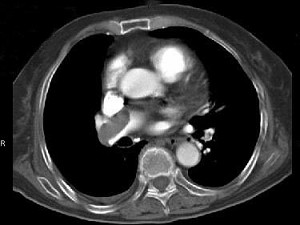

82岁,女性,突发右侧胸痛,呼吸急促,行急诊CT检查,如图所示,请选择最佳答案()

A.中央型肺癌

B.肺门淋巴结肿大

C.肺动静脉瘘

D.肺动脉栓塞

E.肺动脉瘤

[单选题]82岁,女性,突发右侧胸痛,呼吸急促,行急诊CT检查,如图所示,请选择最佳答案()A.中央型肺癌B.肺门淋巴结肿大C.肺动静脉瘘D.肺动脉栓塞E.肺动

[单选题]82岁,女性,突发右侧胸痛,呼吸急促,行急诊CT检查,如图所示,请选择最佳答案()A . 中央型肺癌B . 肺门淋巴结肿大C . 肺动静脉瘘D . 肺动脉栓塞E . 肺动脉瘤

[单选题]82岁,女性,突发右侧胸痛,呼吸急促,行急诊CT检查,如图所示,请选择最佳答案()A .中央型肺癌B .肺门淋巴结肿大C .肺动静脉瘘D .肺动脉栓塞E .肺动脉瘤

[单选题]82岁,女性,突发右侧胸痛,呼吸急促,行急诊CT检查,如图所示:请选择最佳答案()A . 中央型肺癌B . 肺门淋巴结肿大C . 肺动静脉瘘D . 肺动脉栓塞E . 肺动脉瘤